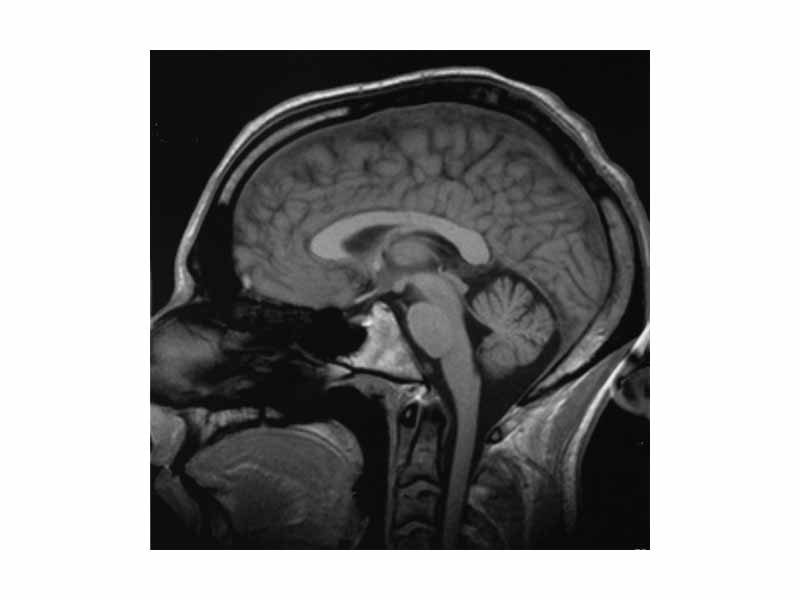

Brain MRI